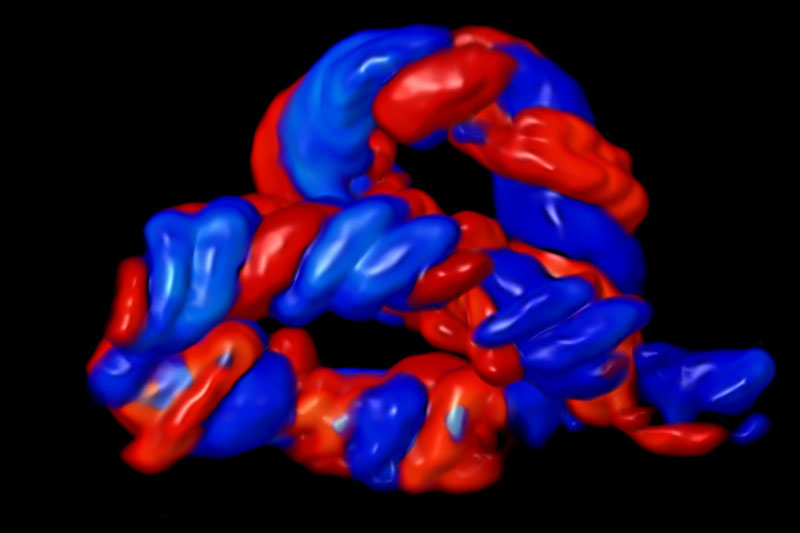

- MRCOG (London) & FMF-UK Certified Operator for NT, NB, DV & Dopplers

FMF-certified scanning protocols, high-resolution ultrasound, and global screening standards.